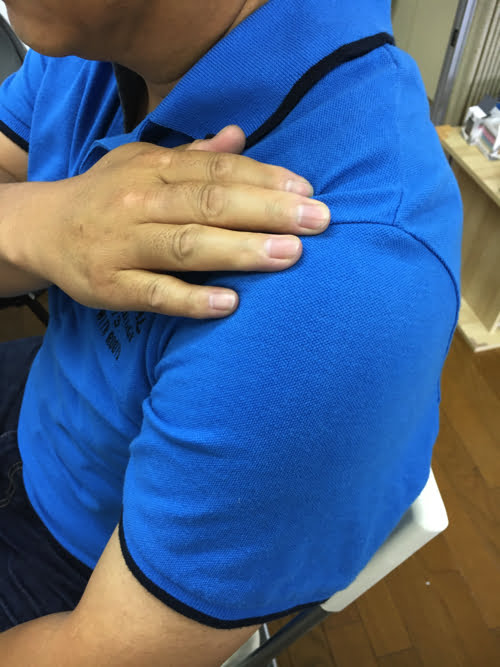

さて今回は、わざわざ山口県から来てくださったお客様。

腕を上げる際に肩の痛みが出るタイプの四十肩。

1年前から左肩が四十肩になり痛かったのですが

初回の治療で随分軽くなりました。

また首も2年前の車の事故からむち打ちのような痛みが

残っていましたが、全く痛くなくなりました。

先生ありがとうございます! また通院したいと思います。